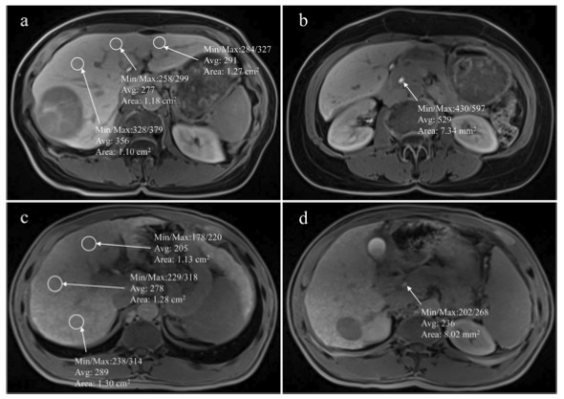

圖 MR圖像顯示了在肝膽期測(cè)量肝臟和膽道系統(tǒng)的信號(hào)強(qiáng)度感興趣區(qū)域的位置。a和b選自一名沒(méi)有出現(xiàn)肝切除術(shù)后肝衰竭的患者。c和d選自一名肝切除術(shù)后出現(xiàn)肝衰竭的患者

本研究在兩個(gè)中心收集了在肝切除術(shù)前接受Gd-BOPTA增強(qiáng)磁共振成像的HCC患者。在肝膽期測(cè)量了膽道系統(tǒng)的相對(duì)增強(qiáng)率(REB)和肝臟與肌肉的比率(LMR)。通過(guò)邏輯回歸分析了PHLF的潛在風(fēng)險(xiǎn)因素,并通過(guò)ROC曲線分析了REB和LMR預(yù)測(cè)PHLF的能力。

在221名患者中,有60名患者(27.1%)發(fā)生肝切除術(shù)后肝衰竭。REB是PHLF的獨(dú)立風(fēng)險(xiǎn)因素(幾率[OR]=0.127[0.047-0.348],P < 0.001)。盡管LMR趨向于與PHLF相關(guān)(P = 0.063),但在多變量分析中,它不是一個(gè)獨(dú)立的危險(xiǎn)因素(OR = 0.624 [0.023-16.709],P = 0.779)。此外,REB和LMR的ROC曲線下的面積為0.87和0.60。REB的最合適截?cái)嘀?/span>為2.21。REB≤2.21的HCC患者比REB>2.21的患者有更高的肝切除后肝衰竭發(fā)生率(60.0%對(duì)8.5%,p < 0.001)。